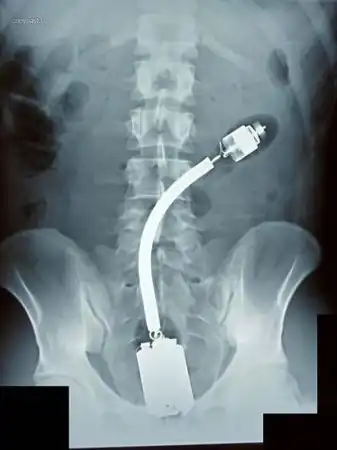

Огромный вибратор в заднице. Залез полностью. Без хирургического вмешательства

достать не смогли. Больные люди...